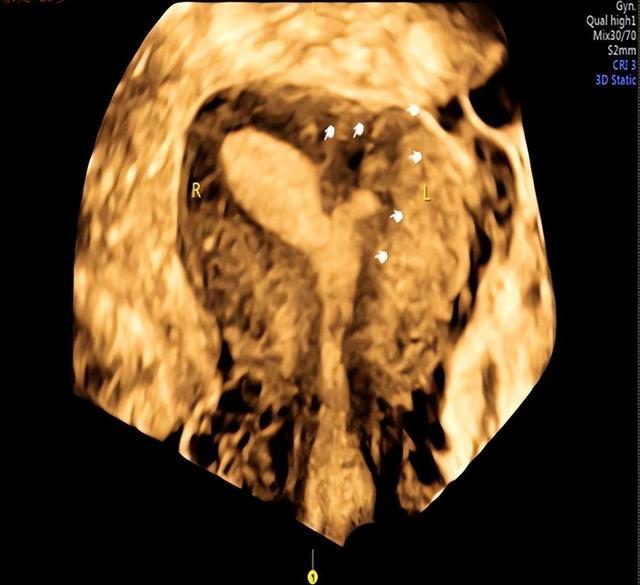

下图的左侧宫角处大面积宫腔粘连,仅见右侧宫腔呈一片树叶状。